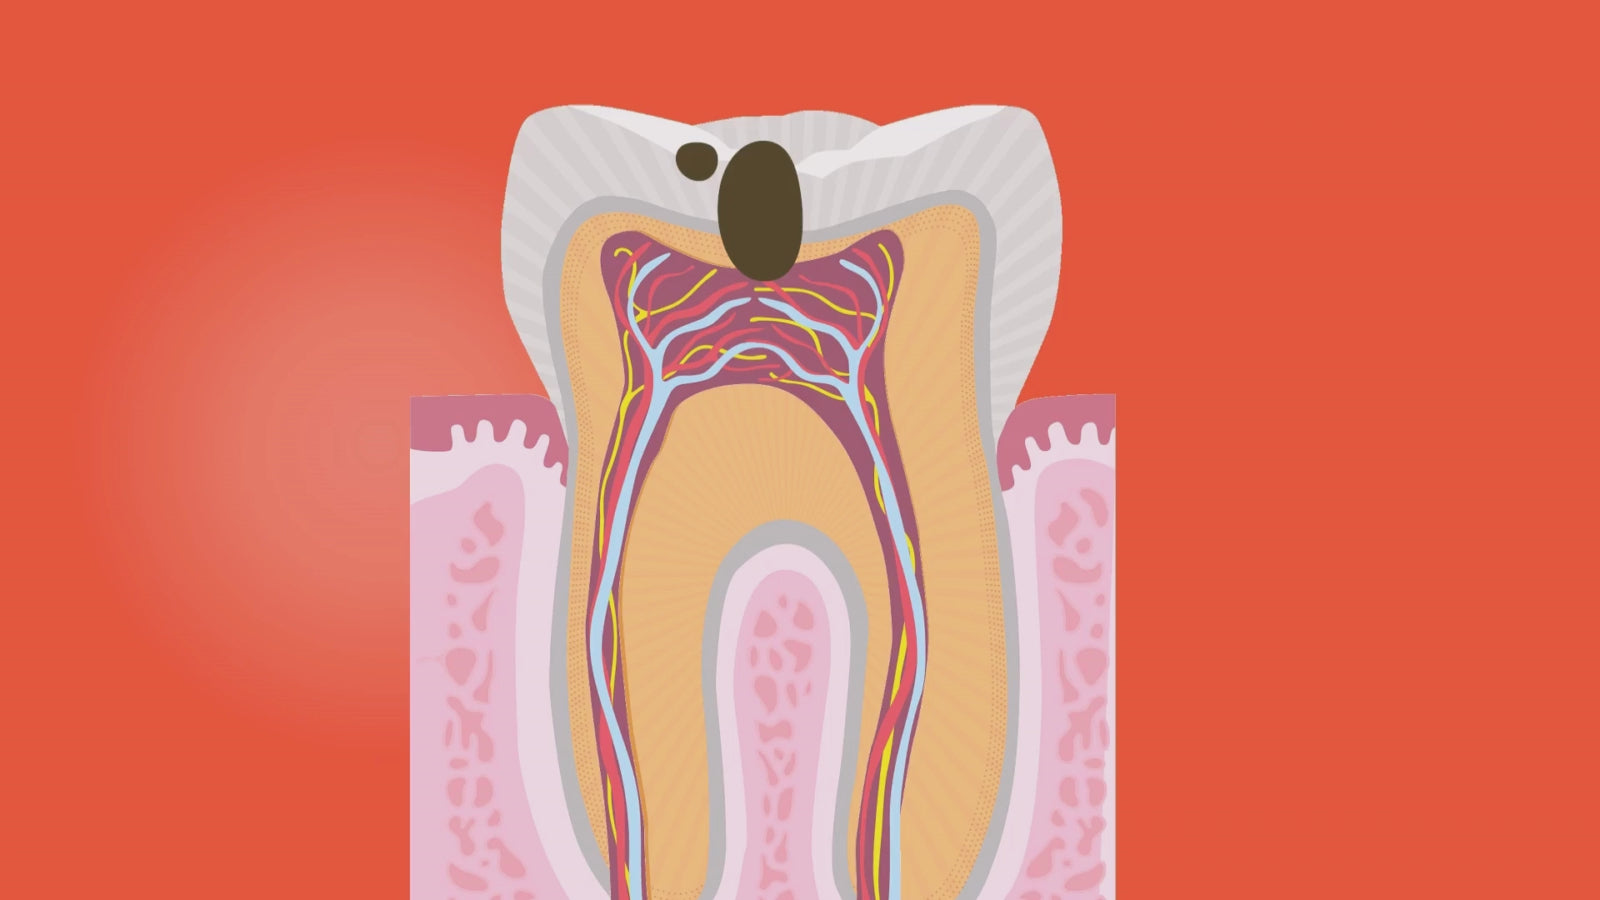

En rotfylling er nødvendig når nerven i tannen er betent, skadet eller død som følge av dype hull, sprekkdannelser eller tidligere traumer. Hos Clinica Tannlegesenter på Majorstuen i Oslo tilbyr vi rotfylling med moderne utstyr og skånsomme teknikker som gir trygg og effektiv behandling – uten unødvendig ubehag.

Målet med rotfylling er å rense rotkanalen grundig og fjerne bakterier og infisert vev, før kanalen fylles med et bakterietett materiale for å hindre ny infeksjon. Behandlingen redder tannen og forhindrer videre komplikasjoner som tannverk, hevelser eller tap av tann.

Trygg rotfylling

Rotfylling behandler effektivt betennelse eller infeksjon dypt inne i tannens rotkanal. Vår tannlege fjerner skånsomt infisert vev, renser grundig, og fyller rotkanalen med et spesialisert materiale som forhindrer videre infeksjon og smerte. Behandlingen er smertefri og gir langsiktige resultater.